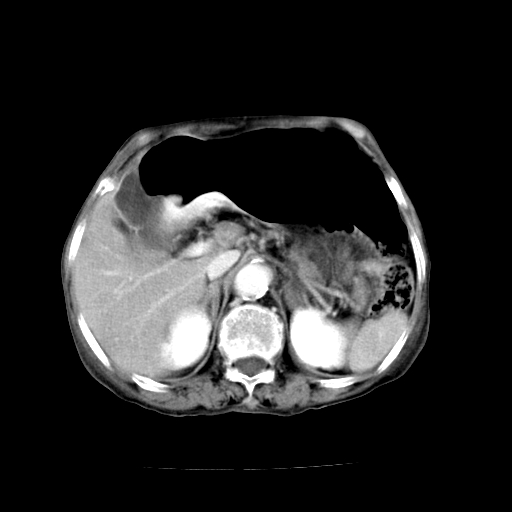

标题: CT19149:女,68岁,腹胀、恶心两周。 [打印本页]

女,68岁,腹胀、恶心两周,先做ct平扫,当时家属不同意强化,6天后家属要求增强扫描。

1、胃窦癌; 2、局灶性脂肪肝。

1、胃窦癌?建议行胃镜!; 2、局灶性脂肪肝。

1.局灶性脂肪肝;2.胃窦癌可能,建议行进一步检查。

考虑:胃窦ca,腹水,脂肪肝

1)胃窦壁厚,考虑胃窦癌?建议行胃镜检查。 2)局灶性脂肪肝。